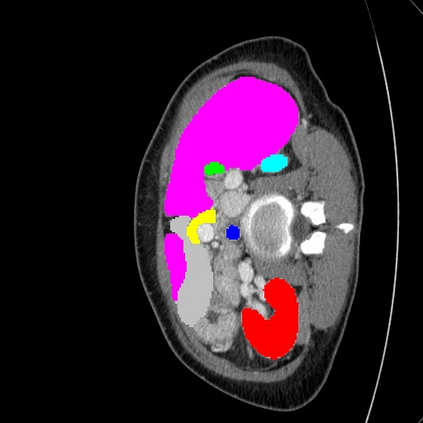

Transformers have made remarkable progress towards modeling long-range dependencies within the medical image analysis domain. However, current transformer-based models suffer from several disadvantages: (1) existing methods fail to capture the important features of the images due to the naive tokenization scheme; (2) the models suffer from information loss because they only consider single-scale feature representations; and (3) the segmentation label maps generated by the models are not accurate enough without considering rich semantic contexts and anatomical textures. In this work, we present CASTformer, a novel type of generative adversarial transformers, for 2D medical image segmentation. First, we take advantage of the pyramid structure to construct multi-scale representations and handle multi-scale variations. We then design a novel class-aware transformer module to better learn the discriminative regions of objects with semantic structures. Lastly, we utilize an adversarial training strategy that boosts segmentation accuracy and correspondingly allows a transformer-based discriminator to capture high-level semantically correlated contents and low-level anatomical features. Our experiments demonstrate that CASTformer dramatically outperforms previous state-of-the-art transformer-based approaches on three benchmarks, obtaining 2.54%-5.88% absolute improvements in Dice over previous models. Further qualitative experiments provide a more detailed picture of the model's inner workings, shed light on the challenges in improved transparency, and demonstrate that transfer learning can greatly improve performance and reduce the size of medical image datasets in training, making CASTformer a strong starting point for downstream medical image analysis tasks.